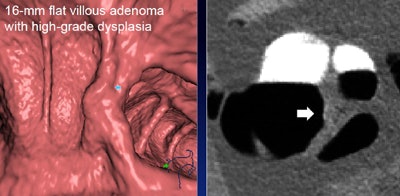

The group applied its advanced CAD algorithm to CTC exams acquired with a minimal-prep protocol and virtual monochromatic dual-energy scanning. The technique detected 96% of 22 colonoscopy-confirmed lesions and 100% of all advanced lesions, with 6.1 false positives per patient for both classifications.

CAD showed 100% sensitivity at a median of three false positives per patient for neoplasms 10 mm and larger, and it detected all significant findings in the 6- to 9-mm lesion category. For neoplasms 10 mm and larger, CAD on dual-energy CT virtual monochromatic images showed a 28% increase in sensitivity (p = 0.001), compared with CAD using conventional single-energy CT, with no increase in false-positive detection. Overall, false positives were 6.1 per patient.